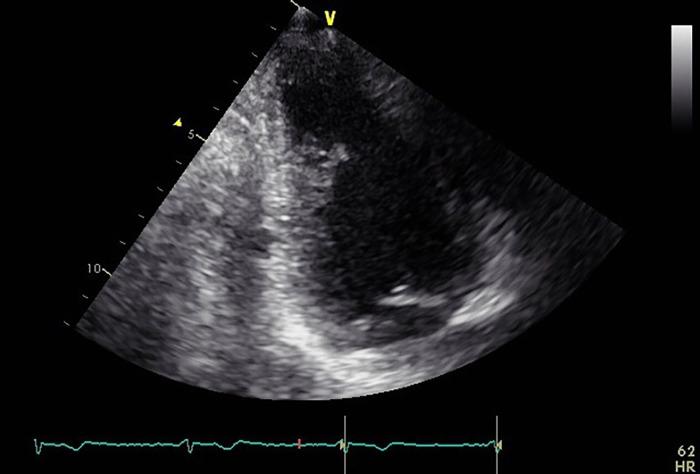

Transthoracic echocardiography is the main imaging modality to diagnose left ventricular thrombus (LVT), but its efficacy in certain cases is suboptimal. We report a patient in whom an LVT, initially unidentified by transthoracic echocardiography, was successfully diagnosed with iodine maps derived from dual-source photon-counting detector CT (DS-PCD-CT). The 64-year-old male was admitted to our institution following myocardial infarction. Although TTE failed to detect this small LVT, iodine maps derived from CT angiography (which was conducted to evaluate the coronary artery stenosis) revealed its presence. Iodine maps derived from DS-PCD-CT collecting data with high temporal resolution are beneficial to diagnose LVTs.

经胸超声心动图是诊断左心室血栓(LVT)的主要成像方式,但在某些情况下其效果并不理想。我们报告了一名患者,其LVT最初经胸超声心动图未识别出,而通过双源光子计数探测器CT(DS-PCD-CT)获得的碘图成功诊断。该64岁男性在心肌梗死后入住我院。尽管经胸超声心动图未能检测到这个小LVT,但为评估冠状动脉狭窄而进行的CT血管造影所获得的碘图显示了其存在。由具有高时间分辨率的数据采集的DS-PCD-CT获得的碘图有助于诊断LVT。